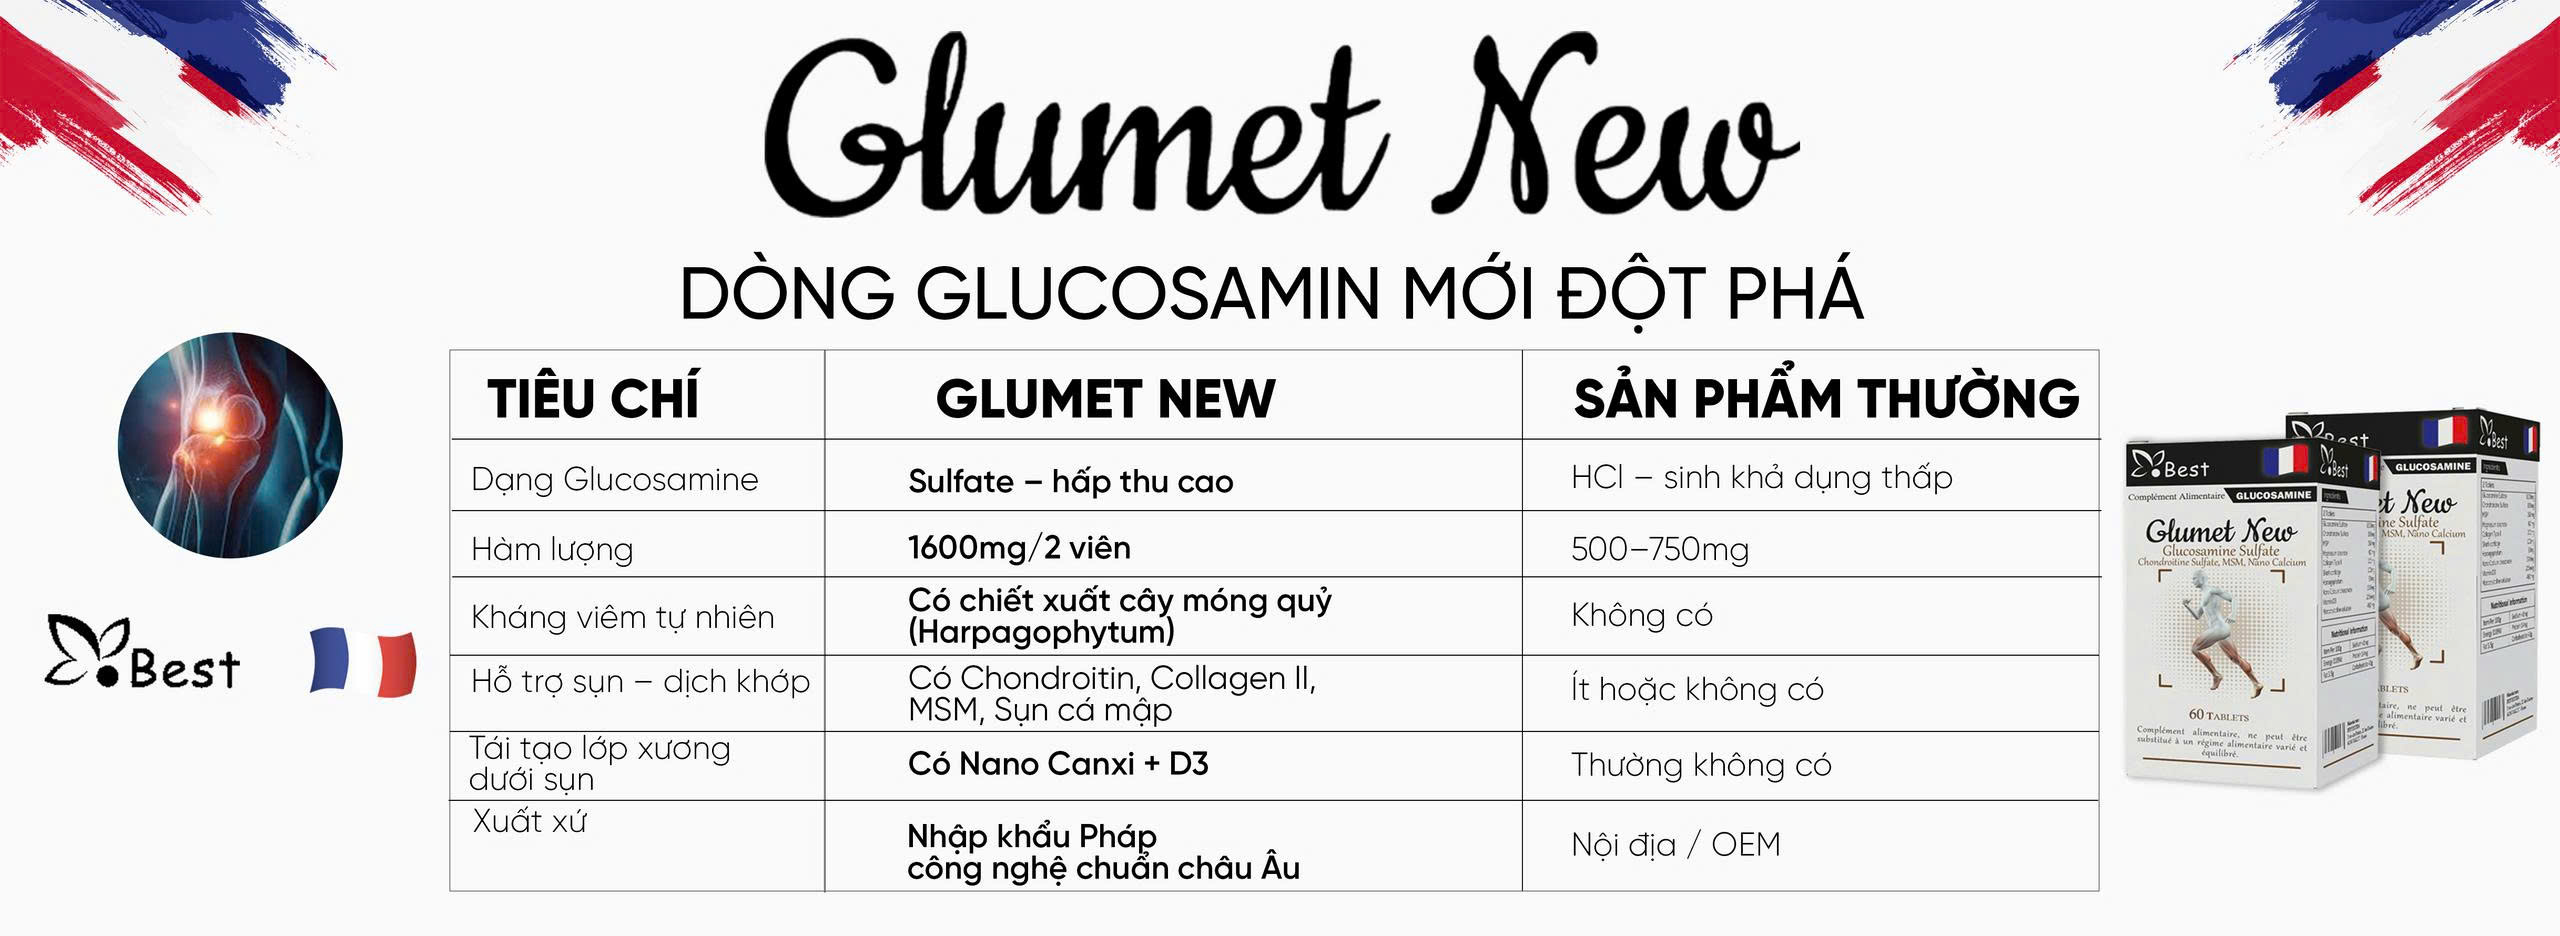

Glucosamine từ lâu đã được coi là “tiêu chuẩn vàng” trong việc hỗ trợ điều trị và phục hồi các bệnh lý về xương khớp. Tuy nhiên, khi dạo quanh các hiệu thuốc hay các trang thương mại điện tử, hàm lượng và thành phần kết hợp. Một câu hỏi lớn đặt ra là: Tại sao có những dòng sản phẩm mang lại hiệu quả rõ rệt, trong khi số khác lại dường như vô thưởng vô phạt? Câu trả lời nằm ở sự khác biệt cốt lõi giữa dạng Glucosamine Sulfate hàm lượng cao 1600mg – tiêu biểu là dòng sản phẩm Glumet New từ Pháp – so với các dòng Glucosamine thông thường khác. Việc thấu hiểu sự khác biệt này không chỉ giúp bạn tối ưu hóa chi phí mà còn là chìa khóa để giảm đau xương khớp một cách khoa học và bền vững.

Trên thị trường hiện nay, Glucosamine chủ yếu tồn tại dưới hai dạng chính là Glucosamine Sulfate và Glucosamine Hydrochloride (HCl). Mặc dù cả hai đều có tác dụng hỗ trợ khớp, nhưng các nghiên cứu lâm sàng quy mô lớn trên thế giới thường ưu tiên sử dụng dạng Sulfate nhờ khả năng hấp thụ và giữ lại trong các mô sụn tốt hơn. Glucosamine Sulfate cung cấp thêm gốc lưu huỳnh (Sulfur) – một nguyên tố cực kỳ quan trọng giúp cơ thể tổng hợp nên các sợi Collagen và Proteoglycan, vốn là hai thành phần chính tạo nên độ dẻo dai cho sụn khớp.

Trong khi nhiều dòng sản phẩm thông thường sử dụng dạng HCl để giảm giá thành sản xuất, Glumet New lại kiên định với dạng Glucosamine Sulfate. Sự khác biệt này giúp sản phẩm không chỉ dừng lại ở việc bổ sung dưỡng chất mà còn thực sự tham gia vào quá trình tái tạo lại những mảng sụn đã bị bào mòn. Việc chọn đúng dạng Sulfate chính là bước đầu tiên để đảm bảo quá trình giảm đau xương khớp an toàn, tránh tình trạng nạp vào cơ thể những hoạt chất khó hấp thụ, gây áp lực lên hệ tiêu hóa và bài tiết mà không mang lại hiệu quả trị liệu thực sự.

Hàm lượng 1600mg và ngưỡng hiệu quả trong điều trị thoái hóa

Một yếu tố then chốt khác tạo nên sự khác biệt của Glumet New chính là hàm lượng hoạt chất. Đa số các dòng Glucosamine thông thường trên thị trường chỉ cung cấp mức hàm lượng từ 500mg đến 1000mg trong một liều dùng. Theo các chuyên gia xương khớp tại Pháp, đây là mức hàm lượng “duy trì”, chưa đủ để kích thích mạnh mẽ quá trình tái tạo mô sụn đối với những người đã bước vào giai đoạn thoái hóa hoặc thường xuyên bị đau nhức. Ngưỡng hàm lượng 1600mg (tương đương với 2 viên Glumet New mỗi ngày) được coi là “ngưỡng hiệu quả” để cơ thể bắt đầu quá trình sửa chữa các vi tổn thương tại ổ khớp.

Sự kết hợp hiệp đồng giữa Glucosamine và chiết xuất thảo dược cây móng quỷ

Sự khác biệt vượt trội của Glumet New so với các dòng Glucosamine thông thường còn nằm ở công thức phối hợp đa tầng. Glucosamine đơn thuần chỉ đóng vai trò là “gạch xây” tái tạo sụn, nhưng để giảm các cơn đau viêm cấp tính một cách tự nhiên, cơ thể cần thêm các chất kháng viêm lành tính. Glumet New đã tích hợp chiết xuất cây móng quỷ (Harpagophytum) – một dược liệu quý từ châu Âu có khả năng ức chế các tác nhân gây viêm mạnh mẽ. Sự xuất hiện của cây móng quỷ giúp người bệnh giảm đau xương khớp an toàn mà không lo ngại các tác dụng phụ gây loét dạ dày như khi dùng thuốc tây.

Bên cạnh đó, MSM (Methylsulfonylmethane) và Chondroitin có trong sản phẩm đóng vai trò là chất bôi trơn và bảo vệ mô liên kết. Sự phối hợp giữa hàm lượng Glucosamine Sulfate 1600mg và các dưỡng chất thảo dược này tạo ra một “vòng tròn bảo vệ” khép kín. Trong khi Glucosamine tái tạo cấu trúc, cây móng quỷ xoa dịu cơn đau, thì MSM giúp tăng tính linh hoạt của các dây chằng quanh khớp. Điều này tạo nên sự khác biệt hoàn toàn so với việc chỉ uống Glucosamine đơn lẻ, vốn thường chỉ mang lại tác động một chiều và chậm phát huy hiệu quả.

Công nghệ Nano Canxi và tiêu chuẩn chất lượng khắt khe từ Pháp

Khác với nhiều dòng sản phẩm hỗ trợ xương khớp thông thường chỉ tập trung vào phần sụn, Glumet New còn chú trọng đến việc củng cố phần xương dưới sụn thông qua công nghệ Nano Canxi. Các phân tử Canxi kích thước siêu nhỏ kết hợp với Vitamin D3 giúp tăng mật độ xương, tạo ra một bệ đỡ vững chắc cho khớp. Nhiều dòng Glucosamine trên thị trường thường bỏ qua yếu tố xương, khiến người dùng dù khớp đã bớt đau nhưng xương vẫn giòn và dễ tổn thương. Việc tích hợp Nano Canxi thân thiện với dạ dày giúp Glumet New trở thành giải pháp chăm sóc hệ vận động toàn diện nhất hiện nay.